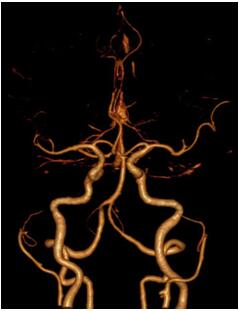

▲CTA未见明显异常